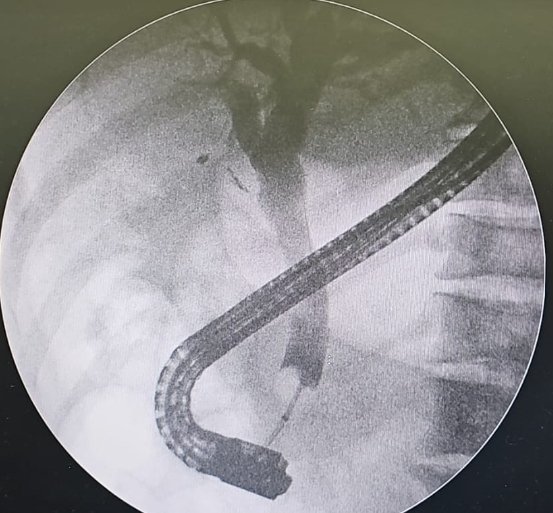

🔴Sphincteroplasty upto 15mm is good strategy to achieve full ductal clearance.This case referred for spyglass;CRE Dilatation 12mm successfully made the duct cleaned. @Almotasembilla1 @AlmuhaidbAymen @CarlKayMD @SyedGerdezi @DrSalihTokmak @drkeithsiau #ERC #Teaching #Cholangitis

Taalamri's tweet image. 🔴Sphincteroplasty upto 15mm is good strategy to achieve full ductal clearance.This case referred for spyglass;CRE Dilatation 12mm successfully made the duct cleaned.